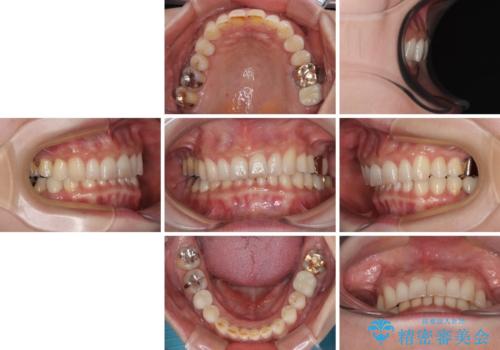

デコボコの歯とむし歯 インビザライン矯正治療とむし歯治療

- 奥歯が咬めないくらいに痛いとのことで来院された患者様です。

痛みの強い歯は、歯髄組織が強い炎症を起こしており、神経を取り除く必要であったため、速やかに根管治療を行いました。

その後、オールセラミッククラウンにて補綴治療を行う予定でしたが、処置した歯以外にも治療が必要と思われる歯があったり、デコボコした歯列も気になるとのことで、患者様希望によりインビザラインにてマウスピース矯正を行うこととしました。

まずは矯正治療前に必要なむし歯処置を行い、その後矯正治療を行ってから、最後にオールセラミッククラウンなどで補綴治療を行うこととしました。

咬合力が非常に強く、全体的に歯が擦り減っている状態であったので、理想的な咬み合わせを達成することは難しく、また咬合力が強い方のマウスピース矯正は、思い通りに動かないことがあるため、ワイヤー矯正の方が望ましいように思えました。

治療途中で2年強、体調を崩されて通院ができなくなってしまったため、必ず通院が必要なワイヤー矯正ではなく、マウスピース矯正で結果的には無事に治療を終えることができました。